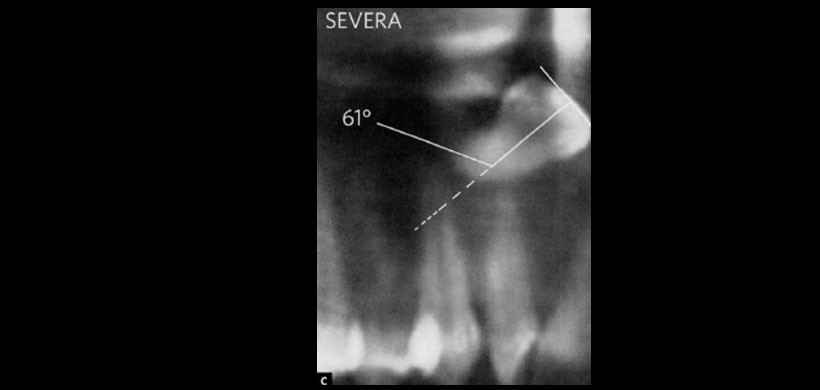

Fig 1. Dilaceración radicular tipo DISCRETA, se considera una angulación de hasta 40°.